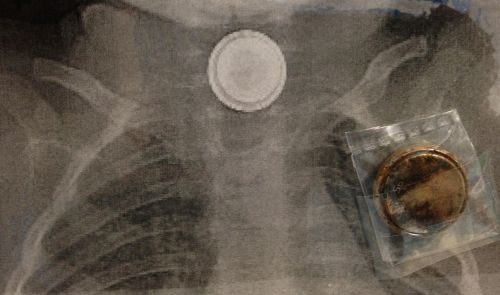

“Aveva ingerito una disk battery, una pila a bottone di uso comune nei videogiochi e in altri dispositivi, senza che i genitori se ne accorgessero. Per questo motivo il piccolo D., quasi 4 anni, ha cominciato manifestare forti dolori addominali che hanno costretto mamma e papà a portarlo al pronto soccorso. Invisibile all’esame ecografico e ad altri tipi di indagini, sono stati i medici dell’Ospedale Pediatrico Bambino Gesù a scoprire la presenza della batteria nell’esofago grazie a una radiografia addominale, effettuata a causa del persistere dei sintomi. E quella batteria, nel corpo del bambino probabilmente già da alcuni giorni, aveva sprigionato la sua carica elettrica bruciando i tessuti e mettendone a rischio la vita. Individuata l’origine del malessere, sono state immediatamente attivate le procedure di emergenza previste dal protocollo nazionale ed europeo per questo tipo di eventi. Si tratta delle linee guida Sigenp ed Espghan-Esge, alla cui stesura hanno partecipato anche gli esperti di Chirurgia Endoscopica Digestiva del Bambino Gesù. Quindi è stata organizzata una équipe multidisciplinare per rimuovere l’oggetto estraneo in condizioni di massima sicurezza”. Lo rende noto l’ospedale pediatrico Bambino Gesù.

La batteria aveva causato gravi ustioni all’esofago e prima di procedere con l’estrazione del corpo estraneo sono state effettuate alcune manovre per verificare la presenza del temuto canale di comunicazione con l’arteria aorta. L’intervento di rimozione per via endoscopica si è concluso senza problemi e il team multidisciplinare non è dovuto ricorrere a nessuna delle misure straordinarie predisposte per gestire un caso clinico così complesso. I successivi esami diagnostici hanno confermato l’assenza di sanguinamenti o di altre complicanze. Il piccolo paziente ha lasciato il reparto di rianimazione ed è in buone condizioni generali. Considerata la possibile insorgenza di emorragie anche a distanza di alcuni giorni, il bambino è rimasto in Ospedale, sotto osservazione, per due ulteriori settimane”.